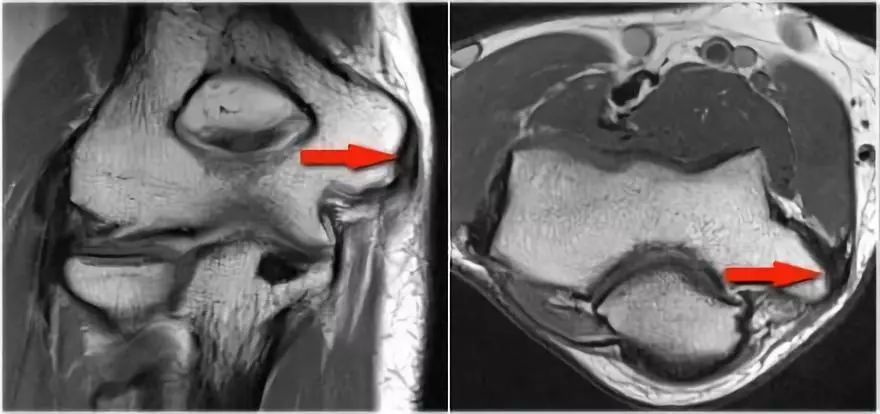

下面是MR● 冠状图片:侧副韧带完全剥离(黄色箭头)。桡骨头是半脱位的。由于骨折引起的冠突骨髓水肿(红色箭头)。● 矢状面观:桡骨头稍后有点半脱位(黄色箭头)。大量积液和囊后破裂。● 由于冠状突的撞击(红色箭头)导致的头颅后侧的挫伤。所有这些迹象都是后脱位的结果。